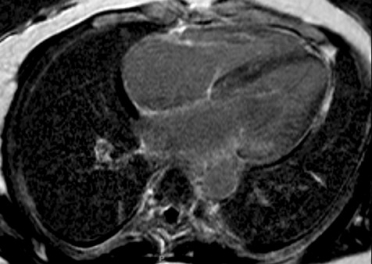

Cardiac magnetic resonance (CMR) imaging with gadolinium contrast can be useful in the identification of cardiac amyloidosis. Late gadolinium enhancement (LGE) occurs as contrast accumulates in the increased extracellular volume (ECV) secondary to amyloid deposition in the myocardium. LGE seen by CMR is one of the most accurate predictors of endomyocardial biopsy-positive amyloidosis [16]. There are a number of other CMR parameters that may be useful for the characterisation of myocardial tissue and possible infiltrative disease [17]. Recent data confirm the utility of the ECV value to assist in the diagnosis of CA [18]. CMR is a good early screening tool for cardiac amyloidosis and can be useful for detecting early fibrosis or infiltration prior to increasing LV thickness (Figure 2 A, B).

Figure 2. Common patterns of hyperenhancement on CMR potentially indicating cardiac amyloidosis. 2A. Diffuse hyperenhancement. 2B. Extensive subendocardial hyperenhancement on cardiac magnetic resonance imaging.

2B.